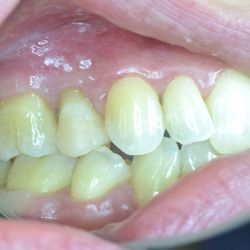

Η νεαρή αυτή ασθενής προσήλθε στο ιατρείο με κάταγμα του παρειακού φύματος του άνω αριστερού προγομφίου.

Το δόντι είχε υποστεί απονεύρωση. Προκειμένου να διαφυλαχθεί η δομική ακεραιότητα του υπολοίπου δοντιού, αποφασίστηκε να αποκατασταθεί το δόντι με εργαστηριακή επένθετη έμφραξη σύνθετης ρητίνης με ελάχιστη αποκοπή οδοντικής ουσίας.

Διατηρήθηκε έτσι ακέραιο το δόντι ενώ η αισθητική του αποκαταστάθηκε απόλυτα.